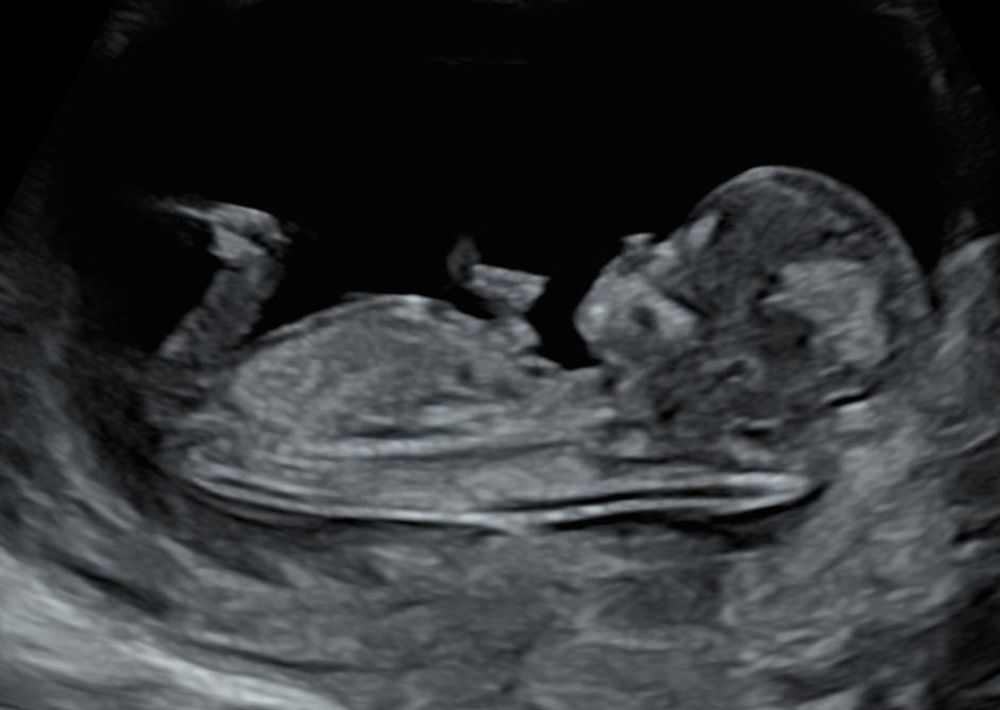

А по УЗИ сказали, что скорей всего девочка. Срок был на УЗИ 12 недель и 4 дня. Я рассмотрела снимки УЗИ и, мне кажется, это девочка 100%. А вам как кажется? Первый снимок чуть жутковатый, добавила второй просто так, красивый профиль)

На первом фото малыш сосет пальчик вроде)) Мне тоже похоже на девочку. У меня тоже такая полосочка на фото в 12 недель в дневнике))

Алена, на первом фото он не сосет пальчик, т.к. лицо повернуто к нам. У вас точно девочка, несколько фото и горизонтальный бугорок. У меня только одно фото в таком ракурсе, где там что-то видно, узистка с большим опытом, не сказала однозначно, поэтому есть микронадежда на мальчика. Это моя первая беременность, поздняя, еще поэтому так тревожно.